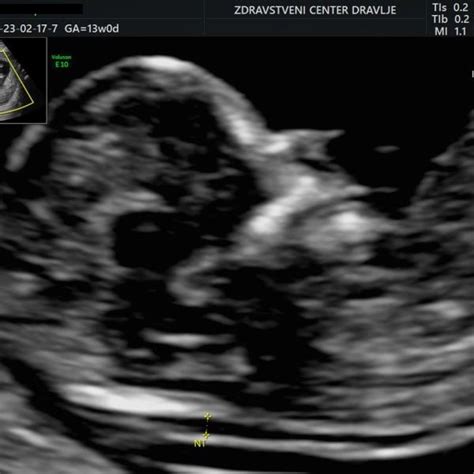

Merjenje nuhalne svetline (11. do 14. teden nosečnosti)

Ultrazvočni pregled med 11. in 14. tednom nosečnosti, znan kot merjenje nuhalne svetline, je ključen za oceno tveganja za kromosomske nepravilnosti, kot je Downov sindrom. Nuhalna svetlina je tanek sloj tekočine pod kožo na vratu ploda. Povečana debelina te svetline lahko nakazuje na povečano tveganje. Ta pregled se pogosto izvaja v sklopu kombiniranega testa, ki vključuje tudi hormonske preiskave iz krvi nosečnice, kar poveča natančnost ocene tveganja. Poleg tega se v tem obdobju izmeri dolžina ploda (teme-trtica), kar omogoča natančnejše določanje pričakovanega datuma poroda.

Pomembno je razumeti, da merjenje nuhalne svetline ni diagnostični test, temveč presejalni. Povečano tveganje ne pomeni nujno prisotnosti kromosomske nepravilnosti, temveč signalizira potrebo po nadaljnjih preiskavah, kot so invazivni diagnostični testi (amniocenteza ali biopsija horionskih resic), če se nosečnica za to odloči.